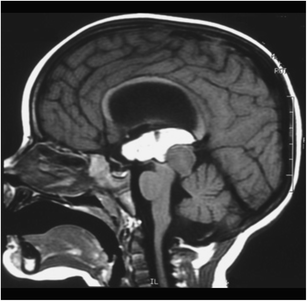

Fig. 20

figure 20

a, b 2-year-old patient evolving to tetraparesis. A large tumor anterior to the medulla is present. The far lateral approach and trans-olivary point of entry was used for resection of a pilocytic astrocytoma. c, d Eleven-year follow-up, showing no evidence of tumor

Fig. 21

figure 21

a, b Cervico-medullary tumor with exophytic extension in the fourth ventricle. c, d MRI at 5 years after surgery shows no evidence of tumor